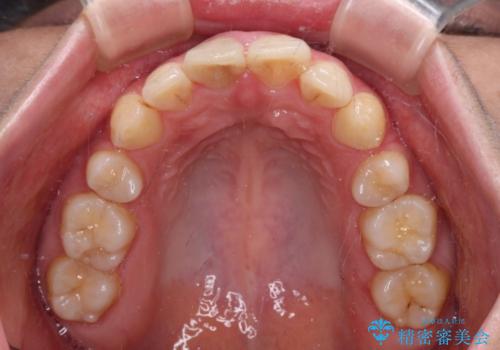

ただし、長期間欠損を放置していたことで、咬み合う上の奥歯が動いてしまっていたので、まずは上顎奥歯の部分矯正を行い、より理想的な咬み合わせを目指すこととしました。

右下の歯は、レントゲン上歯髄組織まで虫歯が及んでいるように見えましたが、痛みの症状は強くなかったため、歯髄組織の一部を断ち歯根部分の組織を保存する生活歯髄療法を第一選択に処置を進めて行くこととしました。

まず生活歯髄療法を行い、その後部分矯正やインプラント処置を行いましたが、最初の処置から1年以上経っても右下奥の処置歯の神経組織に異常は認められませんでした。

部分矯正を行ったことで、違和感のない咬み合わせを達成することができました。